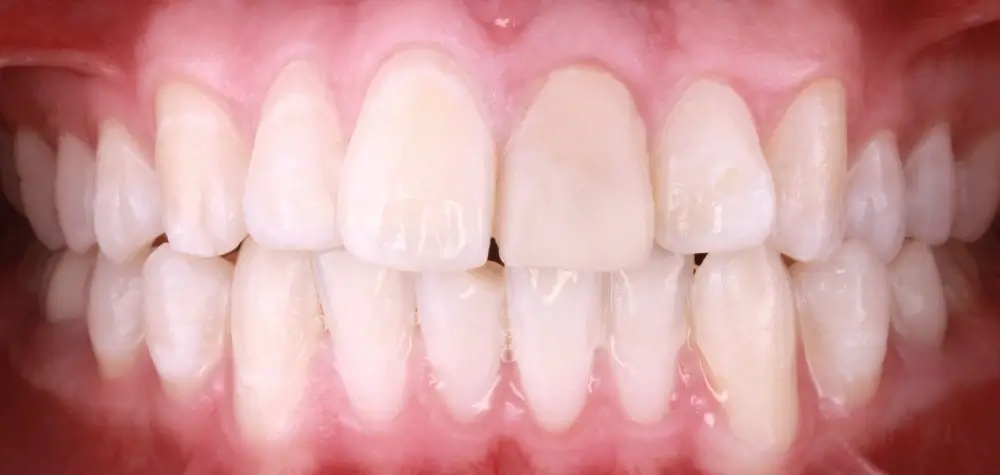

Кейс 9

Бирковская Екатерина Александровна

Количество кап ВЧ 23

Количество кап НЧ 23

ДО

ПОСЛЕ